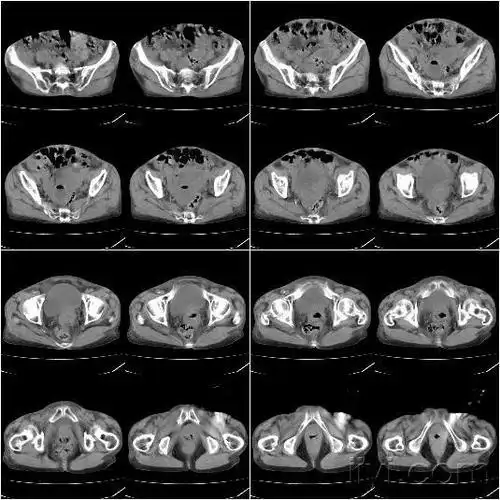

盆腔ct请讨论